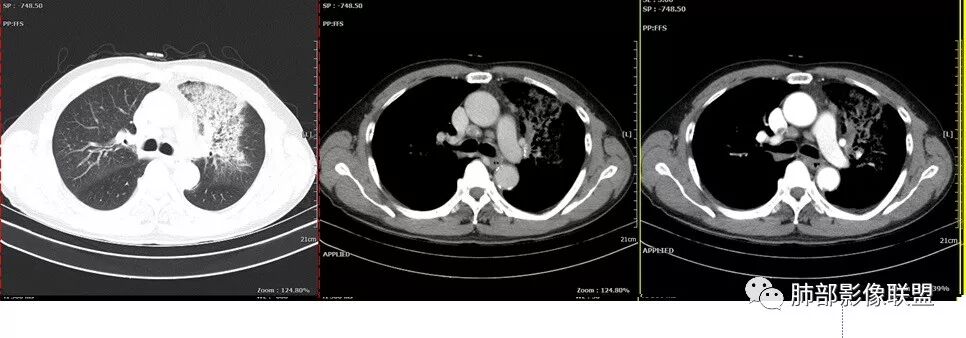

单从影像看,:右肺下叶背段结节并支气管闭塞,肿瘤可能性大;右肺底结节,强化较明显,考虑肉芽肿性病变;左肺上叶大片间质性改变,考虑感染病变;临床提示CRP增高,贫血,糖尿病,单核略高,IGE增高。一元论不好解释。

左上肺大片网格状影,内有实变,内支气管有狭窄和扩张,血管模糊,右下肺有大小多发结节,纵隔有多发淋巴结,部分钙化,还是把肿癌放前面,腺癌?

老年男性,反复咳嗽咳痰十余年,加重伴发热5天,胸痛2天。既往有糖尿病病史。白细胞不高,肝功能受损,CRP及igE明显增高。左肺上叶大片磨玻璃影伴局部实变,支气管通畅,右肺下叶背段近端支气管旁不规则实性结节,轻度均匀强化,背段支气管受压变窄,纵隔及双肺门多发淋巴结肿大并钙化。考虑左上肺感染性病变,先抗感染复查,继续查病原体。右下肺背段结节建议经TBLB活检,排外肿瘤。

胸CT:左肺上叶前段实变,其周围及左肺上叶尖后段可见肺气肿背景下渗出性病变,病灶内可见支气管扩张,气道壁呈不规则增厚,双肺散在小结节状影;右肺下叶结节影,内可见空泡,边缘模糊,不规则。增强可见病灶内血管造影征,右肺门增大,纵隔淋巴结多发肿大。

左肺上叶大片混合网格磨玻璃影,边界清,边缘分叶膨隆,内支气管走行狭窄扩张,实变区边界清,上叶支气管管腔窄,心膈角淋巴结肿大,考虑肺炎型肺癌—腺癌。左肺下肺门结节,边缘膨隆,突入中间段及下叶支气管腔,背段支气管阻塞,周围少量小花小草,考虑鳞癌。右下叶外侧基底段结节,边缘有膨隆,有血管牵拉进入,上缘支气管贴边,考虑肺癌,性质?

晨读:左肺上叶大片实变影,周围可见磨玻璃影,小叶间隔增厚,部分支气管扩张,右肺下叶小结节,形态规则,边缘光滑,周围模糊晕征,中年男性,病史五天,白细胞正常,考虑NTM,奴卡,鉴别肺癌。

患者中老年男性,发热,咳嗽5天,胸痛2天。慢性咳嗽,咳痰10余年,未目前出现活动后胸闷气短,有基础糖尿病、高血压病史,查白细胞正常,CRP增高,IGE增高,CEA轻度增高。胸部CT:左肺上叶片状密度增高影,边界清楚,内见小叶间隔增厚,呈蜂窝网格状,内有磨玻璃影,部分支气管壁增厚,部分有扩张,部分有近段粗细不均;右肺下叶可见一结节影,有凹陷,有膨隆,似有结节感。综合考虑恶性病变,腺癌可能大,鉴别结核。

老年男性,糖尿病病史,crp及ige明显增高,cea轻度增高。影像:左肺上叶前段网格状高密度影,部分实变,部分前段支气管走形僵直。右肺下叶背段近肺门处及右肺下叶外侧基底段各见一枚结节,可见浅分叶,外侧基底段结节可见空泡。纵隔多发淋巴结肿大。综合考虑:肺癌,粘液腺癌?

患者中老年男性,发热,咳嗽5天,胸痛2天。慢性咳嗽,咳痰10余年,目前出现活动后胸闷气短,有基础糖尿病、高血压病史,查白细胞正常,CRP增高,IGE增高,CEA轻度增高。胸部CT:左肺上叶片状密度增高影,边界清楚,内血管穿行,呈蜂窝网格状,内有磨玻璃影,部分支气管壁增厚,部分有扩张,部分有近段粗细不均;右肺下叶可见一结节影,有凹陷,有膨隆,似有结节感,右侧肺门淋巴结肿大,纵隔多发淋巴结肿大、部分伴有钙化。综合考虑恶性病变,左上肺粘液腺癌可能,右下肺小细胞癌?两源论考虑:左上肺粘液腺癌或粘膜相关性淋巴瘤?右下肺结核球伴肺门淋巴结肿。

老年男性,有糖尿病4年,长期咳嗽;这次咳嗽5天,左胸痛2天

这个病灶如何考虑?

纵膈淋巴结以钙化为主。

这个壁厚,但是支气管软骨连续。

背段支气管有问题,局部有结节

膈面上还有一个结节

总共4处病灶,如何考虑?

左上叶肿瘤?炎性?

还有少量胸水。

第一个问题:左上叶考虑炎症?癌?

左肺上叶病灶长轴与支气管走形一致,提示沿支气管分布病变,倾向于炎性,大家可能怀疑这个病例是来源于胸膜下为主的,胸膜下来源首先整体是来源于胸膜下,与胸膜下之间没有间隙,而这例与胸膜下有间隙。而且这个病变是沿支气管朝外蔓延的,而胸膜下来源的是朝内蔓延的,唯一给我们错觉的是靠近纵隔胸膜这个地方有问题。但是靠近纵隔胸膜这个位置实变不是靠近胸膜实变,它边缘收缩的,没有膨隆的迹象。我们看到里面支气管直达远端稍扩张,是以中央间质为主、小叶间隔朝外蔓延,有间质也有实质病变,走向是沿中央间质方向走的,我个人倾向炎性病变。    问题是右下叶病灶怎么解释?右隔上、右肺门各有一个结节。这个病人有急性咳嗽、胸痛的病史,还有糖尿病病史,周围渗出比较明显,应该警惕炎性病变,要警惕克雷伯杆菌、结核、金葡菌霉菌,因为糖尿病人经常好发这些病菌感染。那么右下叶病变怎么考虑?能不能一元论?    左肺病灶是一个急性渗出为主的病变,一个急性感染的迹象;右肺下叶背段结节,没有看到支气管,增强图支气管壁增厚,局部小结节,呈分叶状,支气管堵塞,没有粘液栓样指套样改变,但是里面有强化,我倾向于癌,其次待排结核。我还是倾向于癌的可能性,恶性可能性大一些,可惜我看不到支气管腔内。还考虑有没有淀粉样变性的问题,弥漫钙化灶最常见的一个是结核,另一个是淀粉样变性。叶段支气管壁有弥漫增厚的迹象。所以淀粉样变性跟结核都要考虑。